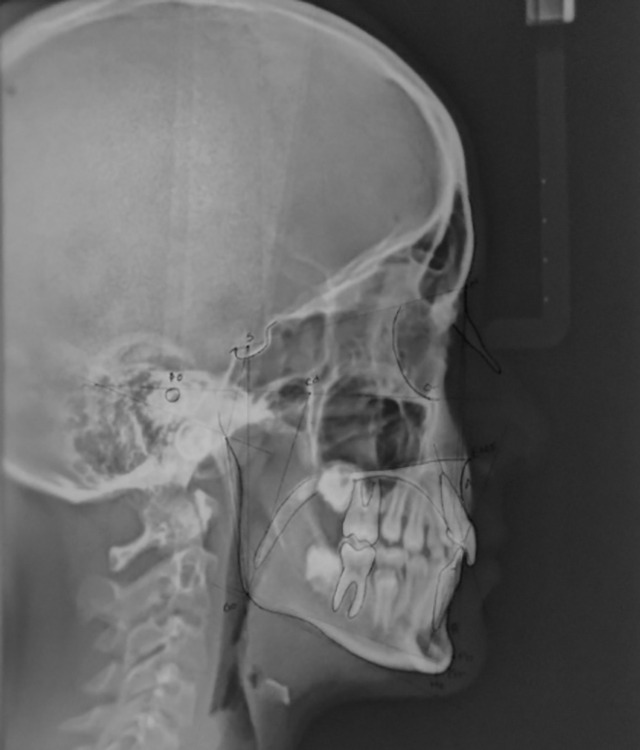

Materials and methods: This cross-sectional study was conducted on a total of 78 participants, aged 4-12 years, with 52 children with adenoid/tonsillar hypertrophy (group I) and 26 healthy children (group II). For each participant, a detailed history of respiratory obstruction or infection was recorded, followed by an orthodontic evaluation. A lateral cephalogram was taken for airway space and cephalometric analysis. Descriptive and inferential statistical tests were computed using SPSS software version 21.

Results: Children with hypertrophic adenoids and tonsils showed a higher incidence of repeated tonsillitis (73.07%) and otitis media (17.3%). On assessing breathing patterns, 88.4% had the mouth breathing habit and 11.5% had the oronasal breathing habit. However, the difference was not statistically significant (p > 0.05). On intergroup comparison, there was a statistically significant difference observed in cephalometric and orthodontic parameters. A higher frequency of lip incompetency, constricted maxillary arch, class II molar relationship, and the posterior crossbite was observed in children with adenotonsillar hypertrophy. Children in group I reported increased overjet (4.9 ± 2.0), increased mandibular plane angle (28.8 ± 3.1), and decreased posterior facial height (61.8 ± 6.1) with a dolichofacial profile (p < 0.05).